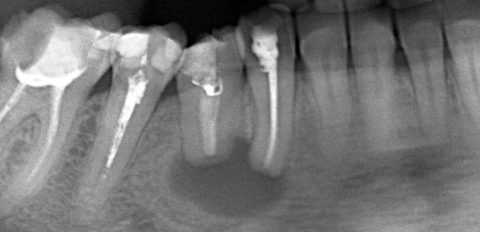

- Рентгенологическое исследование. Рентгенологическая картина заболевания характеризируется однородным участком разжижения костной ткани. Патологический участок, как правило, имеет округлую форму с выраженными краями.

Радикулярная киста в области нижнего моляра и премоляра